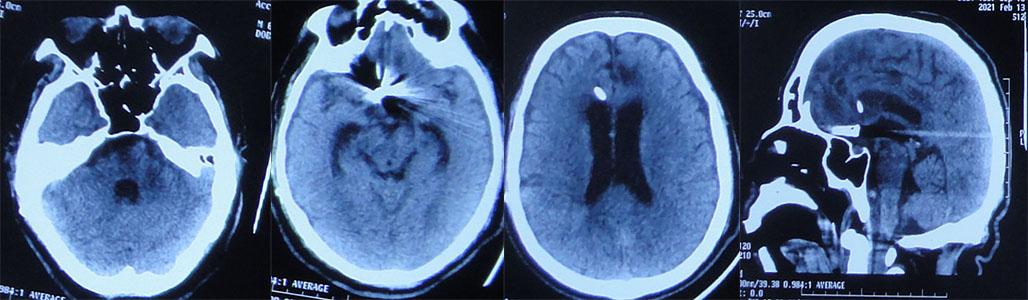

2021年2月13日-2021年3月4日,近1月期间复查两次头部CT脑室大小,没有变化,引流管位置良好( 图-22、图-23 )。

图-22: 2021年2月13日头部CT

图-23: 2021年3月4日头部CT

2021年3月15日(入院120天),进行了脑室腹腔分流术;术前复查头部CT( 图-24 )。

图-24: 2021年3月15日头部CT